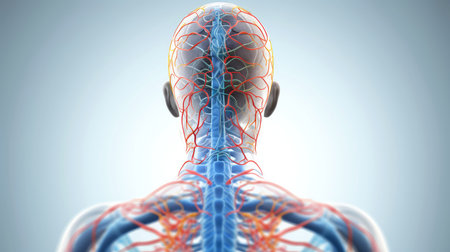

A captivating digital depiction of the human nervous system, highlighting the brain and spinal cord with glowing neural connections, perfect for educational materials.

Vivid visualization of the human nervous system, highlighting brain and spine against dark blue background

This artistic visualization depicts the human anatomy, highlighting the brain, spine, and nervous system in vibrant red hues. Aimed at educational and medical audiences, this model enhances comprehension of human physiology.

AI generated hyper detailed back view of human body showing glowing nerves spinal cord and brain in futuristic sci fi style with high contrast lighting and clean dark background